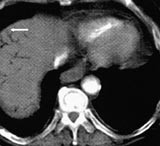

Ved ankomst i sykehuset var han kaldsvettende, forvirret og klaget over smerter i venstre bein. Han hadde ikke buksmerter. Han hadde puls 190/min, uregelmessig, systolisk blodtrykk 210 mm Hg og normal kroppstemperatur. Buken var lett utspilt, uten ømhet eller andre tegn på peritonitt. Venstre bein hadde nedsatt sirkulasjon. EKG viste raskt atrieflimmer. Pasienten var kritisk syk. Behandling av hans raske atrieflimmer med verapamil og metoprolol bedret ikke situasjonen. Blodprøver viste Hb 19,0 g/100 ml (jf. 17,4 g/100 ml to måneder tidligere), leukocytter 21,7 × 10 9 /l, trombocytter 226 × 10 9 /l, CRP 138 mg/l, natrium 141 mmol/l, kalium 3,3 mmol/l, albumin 42,3 g/l, kreatinin 140 µ mol/l, bilirubin 25 µ mol/l, ASAT 262 U/l, ALAT 139 U/l, CK 227 U/l, amylase 139 U/l. CT abdomen viste en normalt kalibrert aorta med tromber i venstre a. iliaca og i a. mesenterica superior. Det forelå en fyllingsdefekt nær avgangen av truncus coeliacus, samt fravær av kontrastfylling i coeliacusgebetet. Forgrening av luft var synlig i leveren (fig 1), helt ut til leverkapselen (fig 2). Luft var også synlig i den ekstrahepatiske del av portvenen, samt i miltvenen og i mesenteriale vener (fig 3). Det forelå ingen utvidelse av magesekken, og heller ingen intramural luft. Vi mistenkte en vaskulær katastrofe i buken. På vei til operasjonsstuen mistet pasienten bevisstheten og døde.